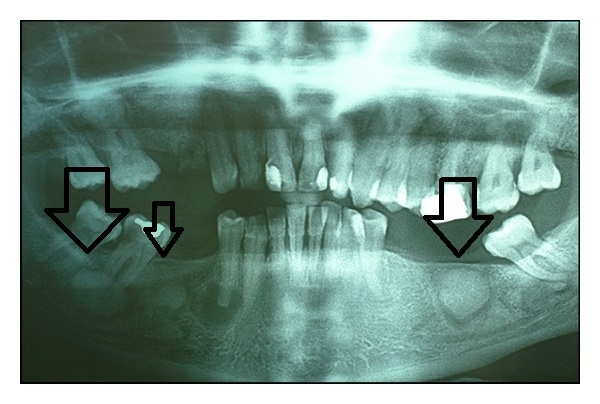

Ectopie Ectopia dentara reprezinta situarea unui dinte(complet sau partial erupt) cu mai mult de 2-3 mm in afara sau inauntrul arcadei dentare. Recomandat:Implanturi dentare moderne: comparații și ghid completImplant vs. punte dentară: ce alegi pentru dinții tăiImplant dentar pas cu pas: ghid complet pentru reușităExtractia dentaraAnchiloza dento-alveolarăCum afectează cafeaua dinții?TaurodontismulRadiografia panoramicăCum se face implant dentar: ghid complet pentru 2026ApexificareaCoroana dentară sau implant? Soluții moderne în 2026Decolorarea dinților temporariSemne care indică necesitatea unui aparat dentarLista servicii dentist București: alegerea corectă în 2026Indicațiile extracției dentarePericoronaritaTestarea sensibilității pulpareIstoria aparatului dentarÎngrijirea protezei dentareÎngrijirea dinților în vacanțăCementoblastomulCe este implantul dentar: ghid complet pentru bucureșteni